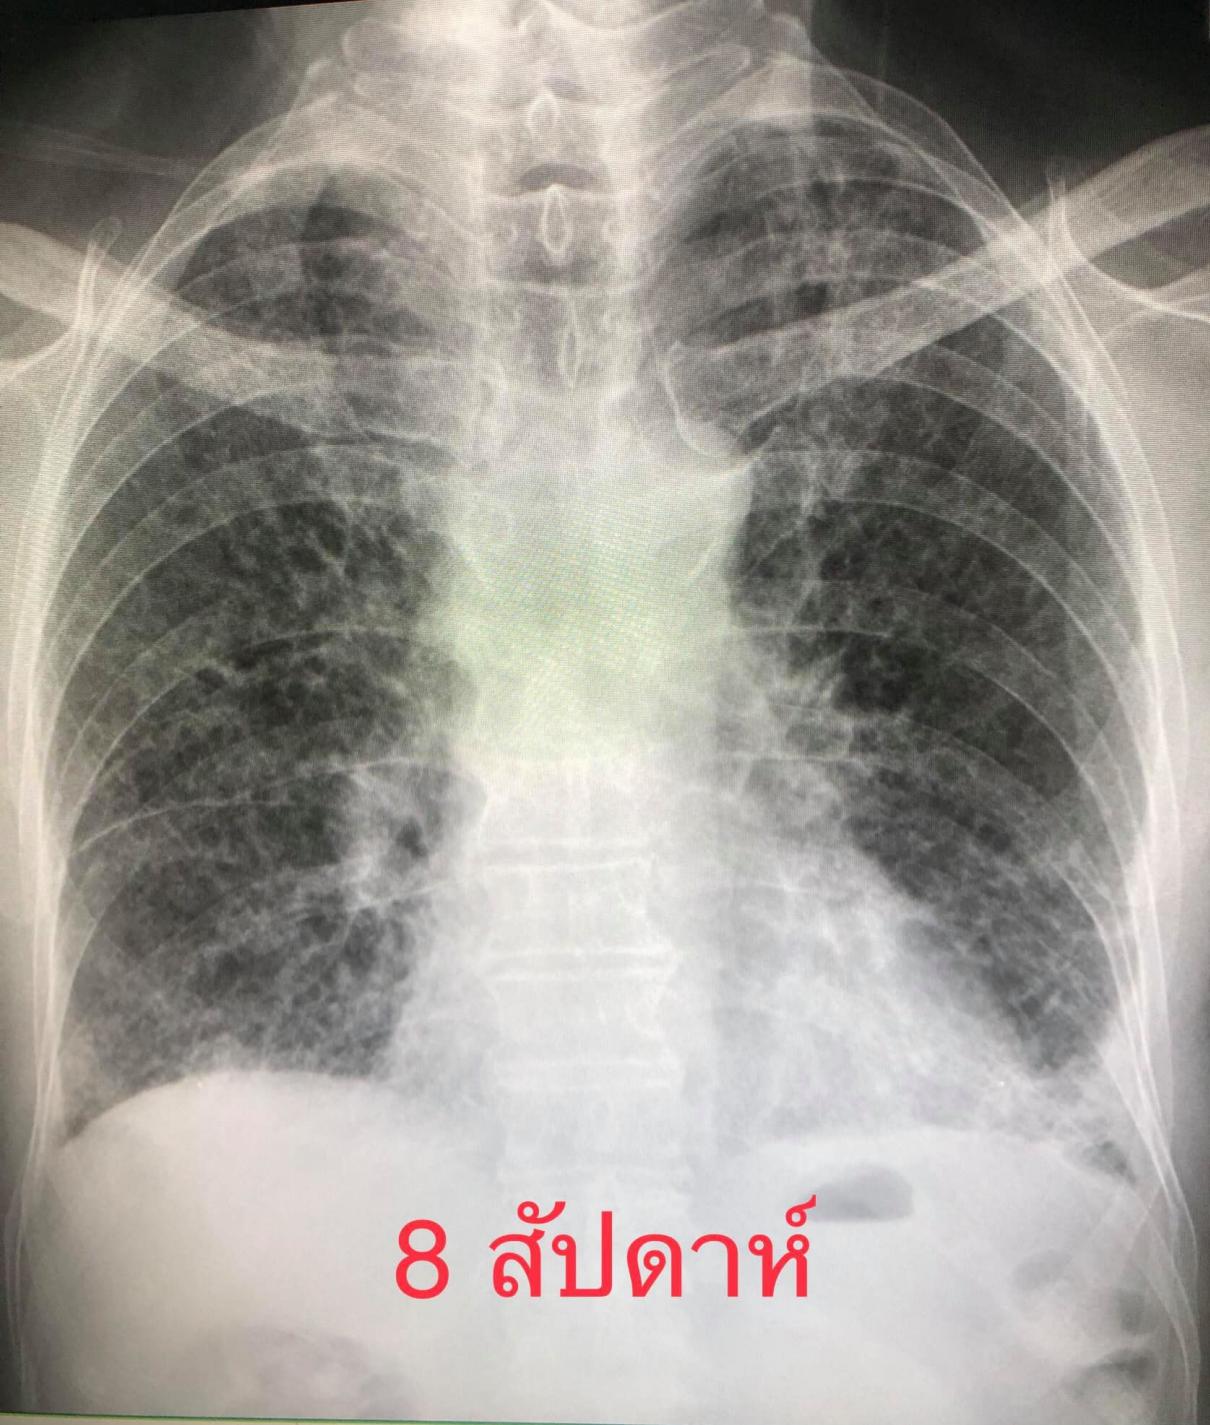

ผู้ป่วยชายไทยอายุ 80 ปี ปกติแข็งแรงดี ไม่มีประวัติป่วยเป็นโรคปอด ไม่สูบบุหรี่ เมื่อวันที่ 16 เมษายน 2564 ป่วยเป็นโรคโควิด-19 โดยลูกเป็นคนนำเชื้อมาให้ผู้ป่วยและคนในครอบครัวรวมทั้งหมด 7 คน เข้านอนรักษาในโรงพยาบาลด้วยปอดอักเสบรุนแรง เอกซเรย์ปอดมีฝ้าขาวทั้ง 2 ข้าง (ดูรูป) ทำคอมพิวเตอร์สแกนปอดพบเนื้อเยื่อปอดอักเสบรุนแรง มีทั้งฝ้าขาว รอยโรคเหมือนร่างแห และลักษณะผิดปกติคล้ายรังผึ้ง กระจายทั่วปอด (ดูรูป) ผู้ป่วยได้รับการรักษาเต็มที่ โชคดีที่ไม่ต้องใส่เครื่องช่วยหายใจ ต้องใช้ออกซิเจนมากถึง 10 ลิตร/นาทีตลอดเวลา นอนในรพ.ถึงวันที่ 22 พฤษภาคม 2564